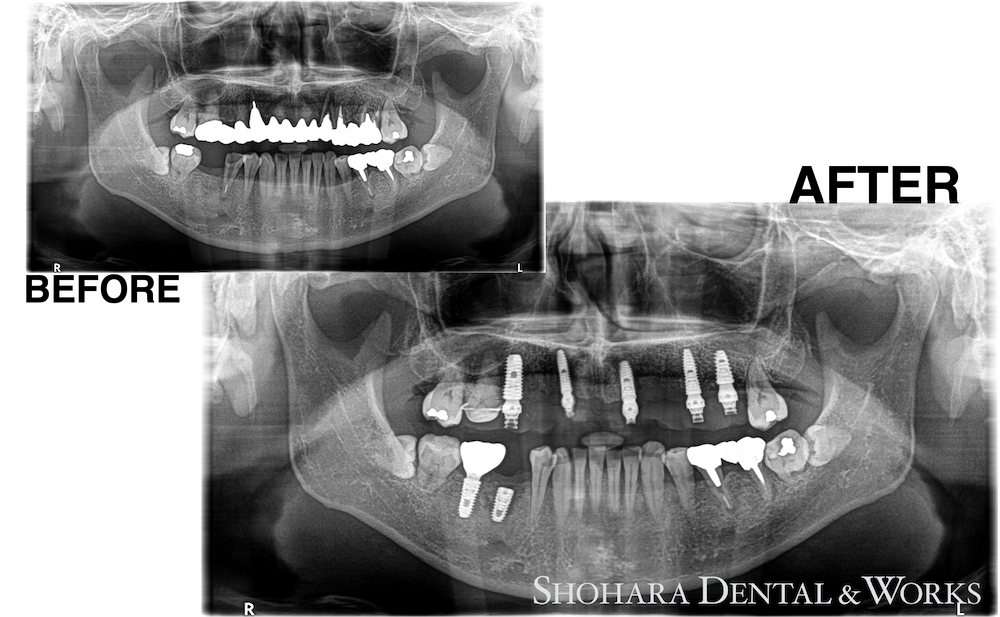

術前・術後のレントゲン写真

| 治療説明 | 上顎前歯部ブリッジ撤去、抜歯を行い同時にインプラントを5本埋入。初期固定が得られたのを確認し、プロビジョナルで即時補綴を行った。待機期間3ヶ月ののち、印象を行い、ジルコニアブリッジを装着した。 |